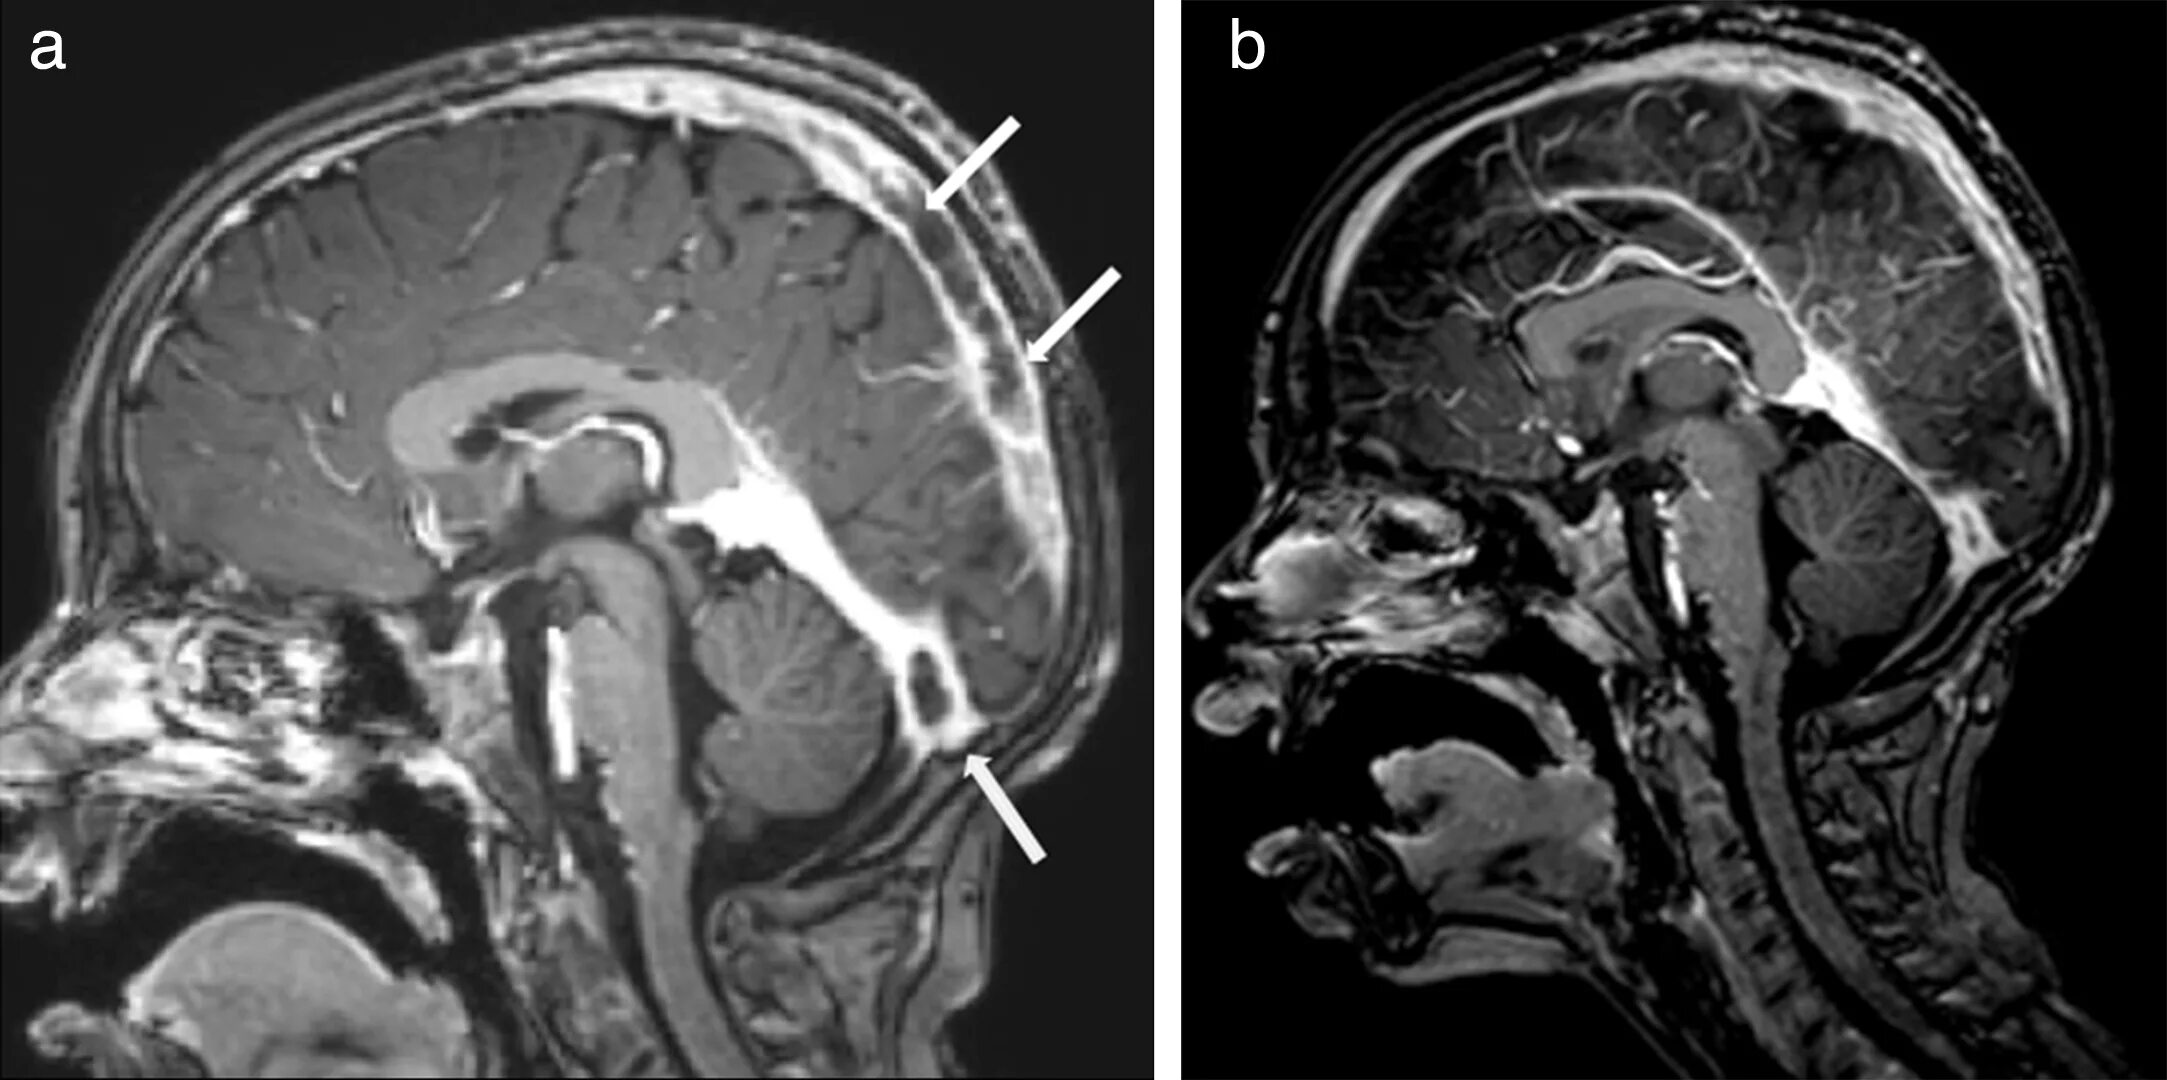

Синусы мозга мрт